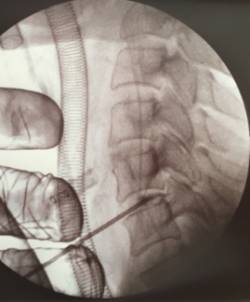

Mediante una mínima incisión en la piel y un endoscopio de menos de 5 mm de diámetro se pueden visualizar todas las estructuras de la columna cervical y abordar de forma segura la hernia discal. La visualización de todas las estructuras anatómicas de la columna, mediante una cámara de alta definición e irrigación continua, facilita al cirujano un trabajo seguro y preciso en la columna cervical. El Morgenstern Institute of Spine fue pionero en practicar este tipo de intervenciones en la columna lumbar con excelentes resultados y ahora la ha aplicado con éxito en la columna cervical para tratar una triple hernia discal cervical.